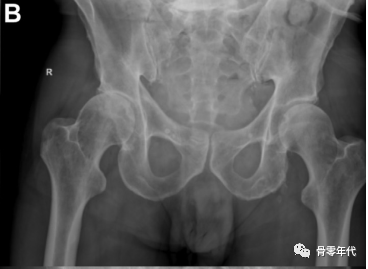

用于目标肢体延长的关节炎严重程度分级。(A)关节间隙轻度变窄的目标是延长2-3 mm。(B)完全缩小关节间隙的目标是加长4-5mm。(C)股骨头扁平或髋臼骨质侵蚀可延长5~6mm。(D)股骨头和髋臼侵蚀的目标是延长6mm或更长。